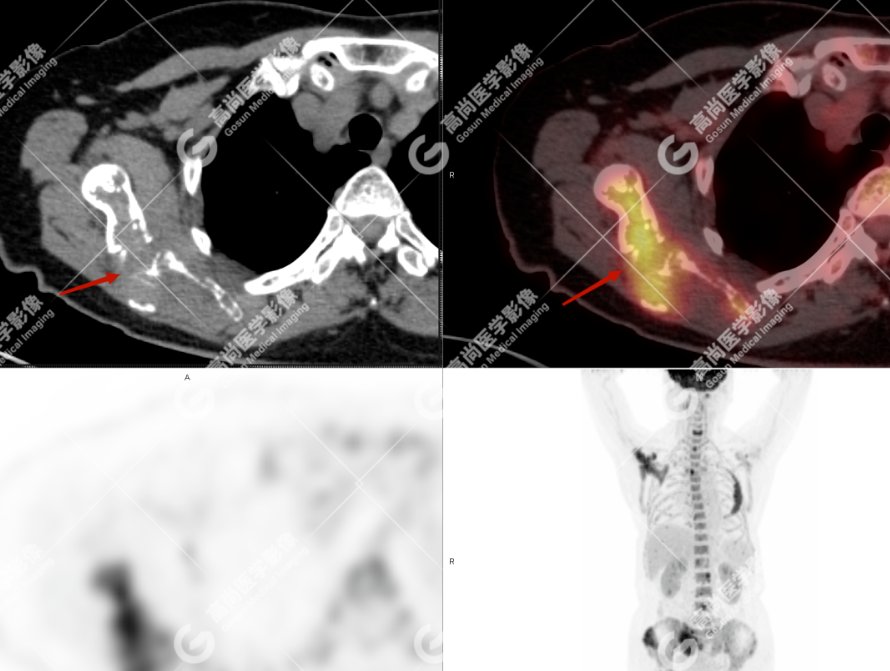

颅骨、寰椎前弓左侧份、第 6 颈椎、双侧肩胛骨(右侧为著)、左侧第 4 肋骨、第 1 胸椎、第 4 胸椎、第 2 腰椎及附件、第 4 腰椎及附件、骶骨、右侧髂骨、左侧坐骨结节、左侧股骨颈、双侧股骨小转子等均不同程度骨质吸收、破坏,其中右侧肩胛骨、左侧第 4 肋骨及骶骨右侧份软组织肿块影形成,上述病变均考虑恶性肿瘤(血液系统来源,多发骨髓瘤可能性大),建议右侧髂骨翼穿刺活检明确。

(4)PET-CT 影像表现:在溶骨性破坏区出现相重叠的 18F- FDG 高代谢区;通常呈弥漫性高代谢区。